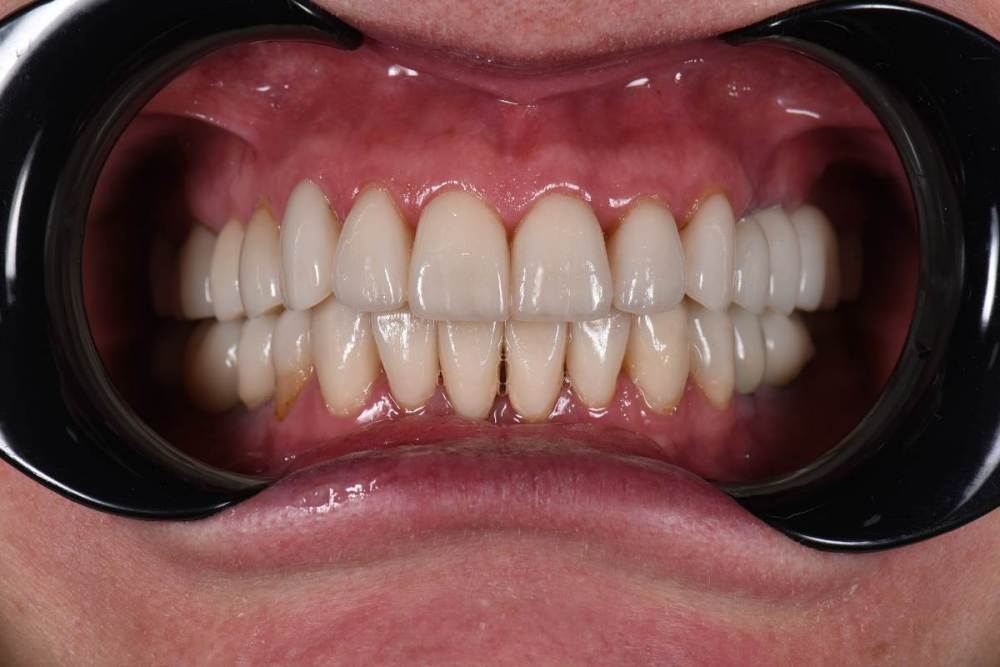

Финиш:

754622731_.thumb.JPG.76220528fdc535799b6fa325a0584dbb.JPG

2065806015_.thumb.JPG.2c9893b4ad1989d5149e8449c9038fac.JPG

DSC_0583.thumb.JPG.66f2923d0f8eca2a1db42be467c63bfb.JPG

Закончил тотал и решил поделиться. Протезировали с учетом положения ВНЧС в концепции Славичека.  В конце изготовление брукс чекеров для проверки нежелательных контактов во время сна.  Гигиену пытаемся победить...